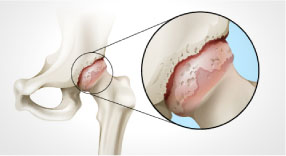

Wear porc - a fő oka a betegségek az ízületek (artritisz, artritisz, synovitis, osteochondrosis, stb ...). Vékony, száraz porc nem képes megvédeni az ízületi felületeket és a közös bomlani kezd, és deformálódhat. Ízületi betegség önmagában nem halad. A következmény gondatlan magatartása és kezelés hiánya vezet a progresszió izületroncsolódás.

megsemmisítés

porcogó

ízületek